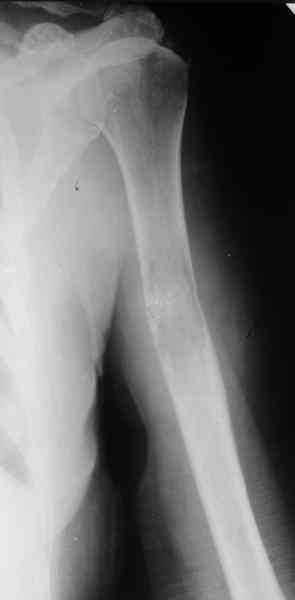

Женщина 53 лет получила патологический перелом правого плеча в феварле, и левого в марте - mts из невыясненного первичного очага.

Онкологи провели облучение, руки на косынки, время от времени наблюдают, вводили зомету.На нас вышли родственники. Состояние пациентки уже не очень, анемия (Hb -50-60 г/л), исхудалв, но асцита нет, в легких чисто. Поскольку женщина совершенно беспомощна, решили сделать остеосиннтез.

Сегодня сделали, Fixion диаметром 7,4 мм. Обе пперации продолжались по 7 мин. Картинки в приложении. Наркоз был диприваном, на спонтанном дыхании. По крайней мере, пока довольны хотя бы анестезиологи, похоже, не верили, что управимся меньше, чем за час ;-)

Гвоздик 7,4 расширяется до 11 мм. Не маловато ли, судя по снимкам?

Обсалютным показанием для использования этого стержня,из моей практики, являетются поперечные переломы диафиза пдечевой и большеберцовой костей.Преимущество его в удобстве репозиции и продалжительности операчии.Недостаток в сдабой ротационной стабильности.Учитывая состояние больной,метод был выбран правильно.Мы этих больных оперируем тогда когда приблизительный срок выживания превышает шесть месяцев и конечно же всотрудничестве с окологами.

7,4 мм, рсширяющийся до 11 мм, в принципе, достаточно для плеча. Хотя мне тоже показалось, что можно было бы и потолще. Вообще есть и следующий диаметр, 8,5 мм, расширяющийся до 13,5 мм, но его в наличии на сегодня не было.